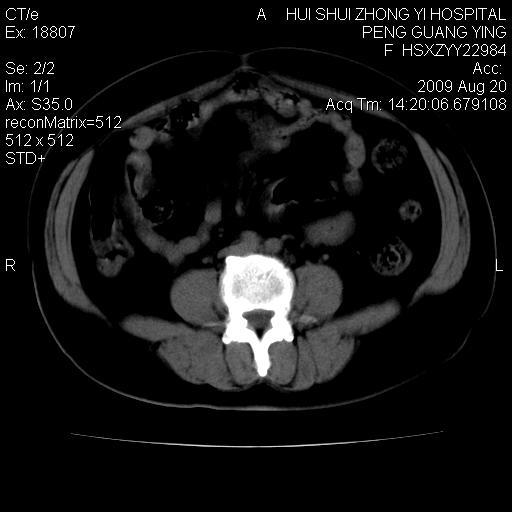

标题: CT21707:女,42岁,因发现下腹部包块2月。 [打印本页]

标题: CT21707:女,42岁,因发现下腹部包块2月。

病灶来源——子宫?附件?

从平扫角度看本人还是倾向于子宫肌瘤诊断,宫腔少量积液。

目前的影像表现显示肿块位于腹腔及盆腔,但具体定位,分清来源较困难,是否来源于卵巢、子宫无法定论,子宫直肠及子宫膀胱周围脂肪间隙尚较清晰,如果患者有过腹腔好或者盆腔手术史,也可以形成不典型的血中,最好手术后定为定性,我期待结果。

软组织密度,与子宫一致。双侧卵巢形态、密度好,不支持来源于卵巢。

病史不全面,病灶来源可能是子宫或卵巢,若临床有剖腹产、痛经史,则更支持前者,亦更支持子宫腺肌症